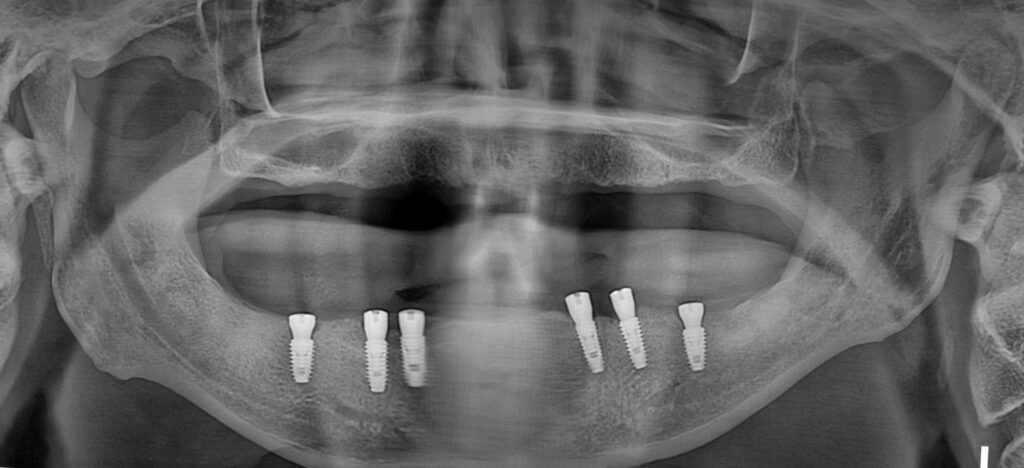

아래턱에 먼저 여섯 개 임플란트를 심었고요.​

다음에 오셨을 때 위턱에 7개 임플란트를 심었습니다.

전체 임플란트를 진행할 때

위에는 최소 7개가

아래에는 최소 6개가 필요합니다

임플란트 보철까지 깔끔하게 잘 올라간 모습을 볼 수 있습니다.

​또한 상악동 거상술을 이용해 만든 뼈도 단단하게 자기 뼈가 되고 있는 모습을 볼 수 있습니다.